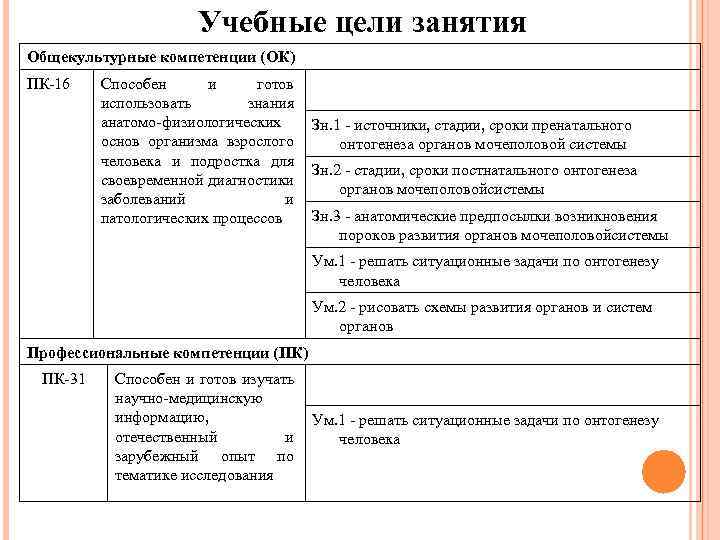

Учебные цели занятия Общекультурные компетенции (ОК) ПК-16 Способен и готов использовать знания анатомо-физиологических Зн. 1 - источники, стадии, сроки пренатального основ организма взрослого онтогенеза органов мочеполовой системы человека и подростка для Зн. 2 - стадии, сроки постнатального онтогенеза своевременной диагностики органов мочеполовойсистемы заболеваний и Зн. 3 - анатомические предпосылки возникновения патологических процессов пороков развития органов мочеполовойсистемы Ум. 1 - решать ситуационные задачи по онтогенезу человека Ум. 2 - рисовать схемы развития органов и систем органов Профессиональные компетенции (ПК) ПК-31 Способен и готов изучать научно-медицинскую информацию, Ум. 1 - решать ситуационные задачи по онтогенезу отечественный и человека зарубежный опыт по тематике исследования

Учебные цели занятия Общекультурные компетенции (ОК) ПК-16 Способен и готов использовать знания анатомо-физиологических Зн. 1 - источники, стадии, сроки пренатального основ организма взрослого онтогенеза органов мочеполовой системы человека и подростка для Зн. 2 - стадии, сроки постнатального онтогенеза своевременной диагностики органов мочеполовойсистемы заболеваний и Зн. 3 - анатомические предпосылки возникновения патологических процессов пороков развития органов мочеполовойсистемы Ум. 1 - решать ситуационные задачи по онтогенезу человека Ум. 2 - рисовать схемы развития органов и систем органов Профессиональные компетенции (ПК) ПК-31 Способен и готов изучать научно-медицинскую информацию, Ум. 1 - решать ситуационные задачи по онтогенезу отечественный и человека зарубежный опыт по тематике исследования